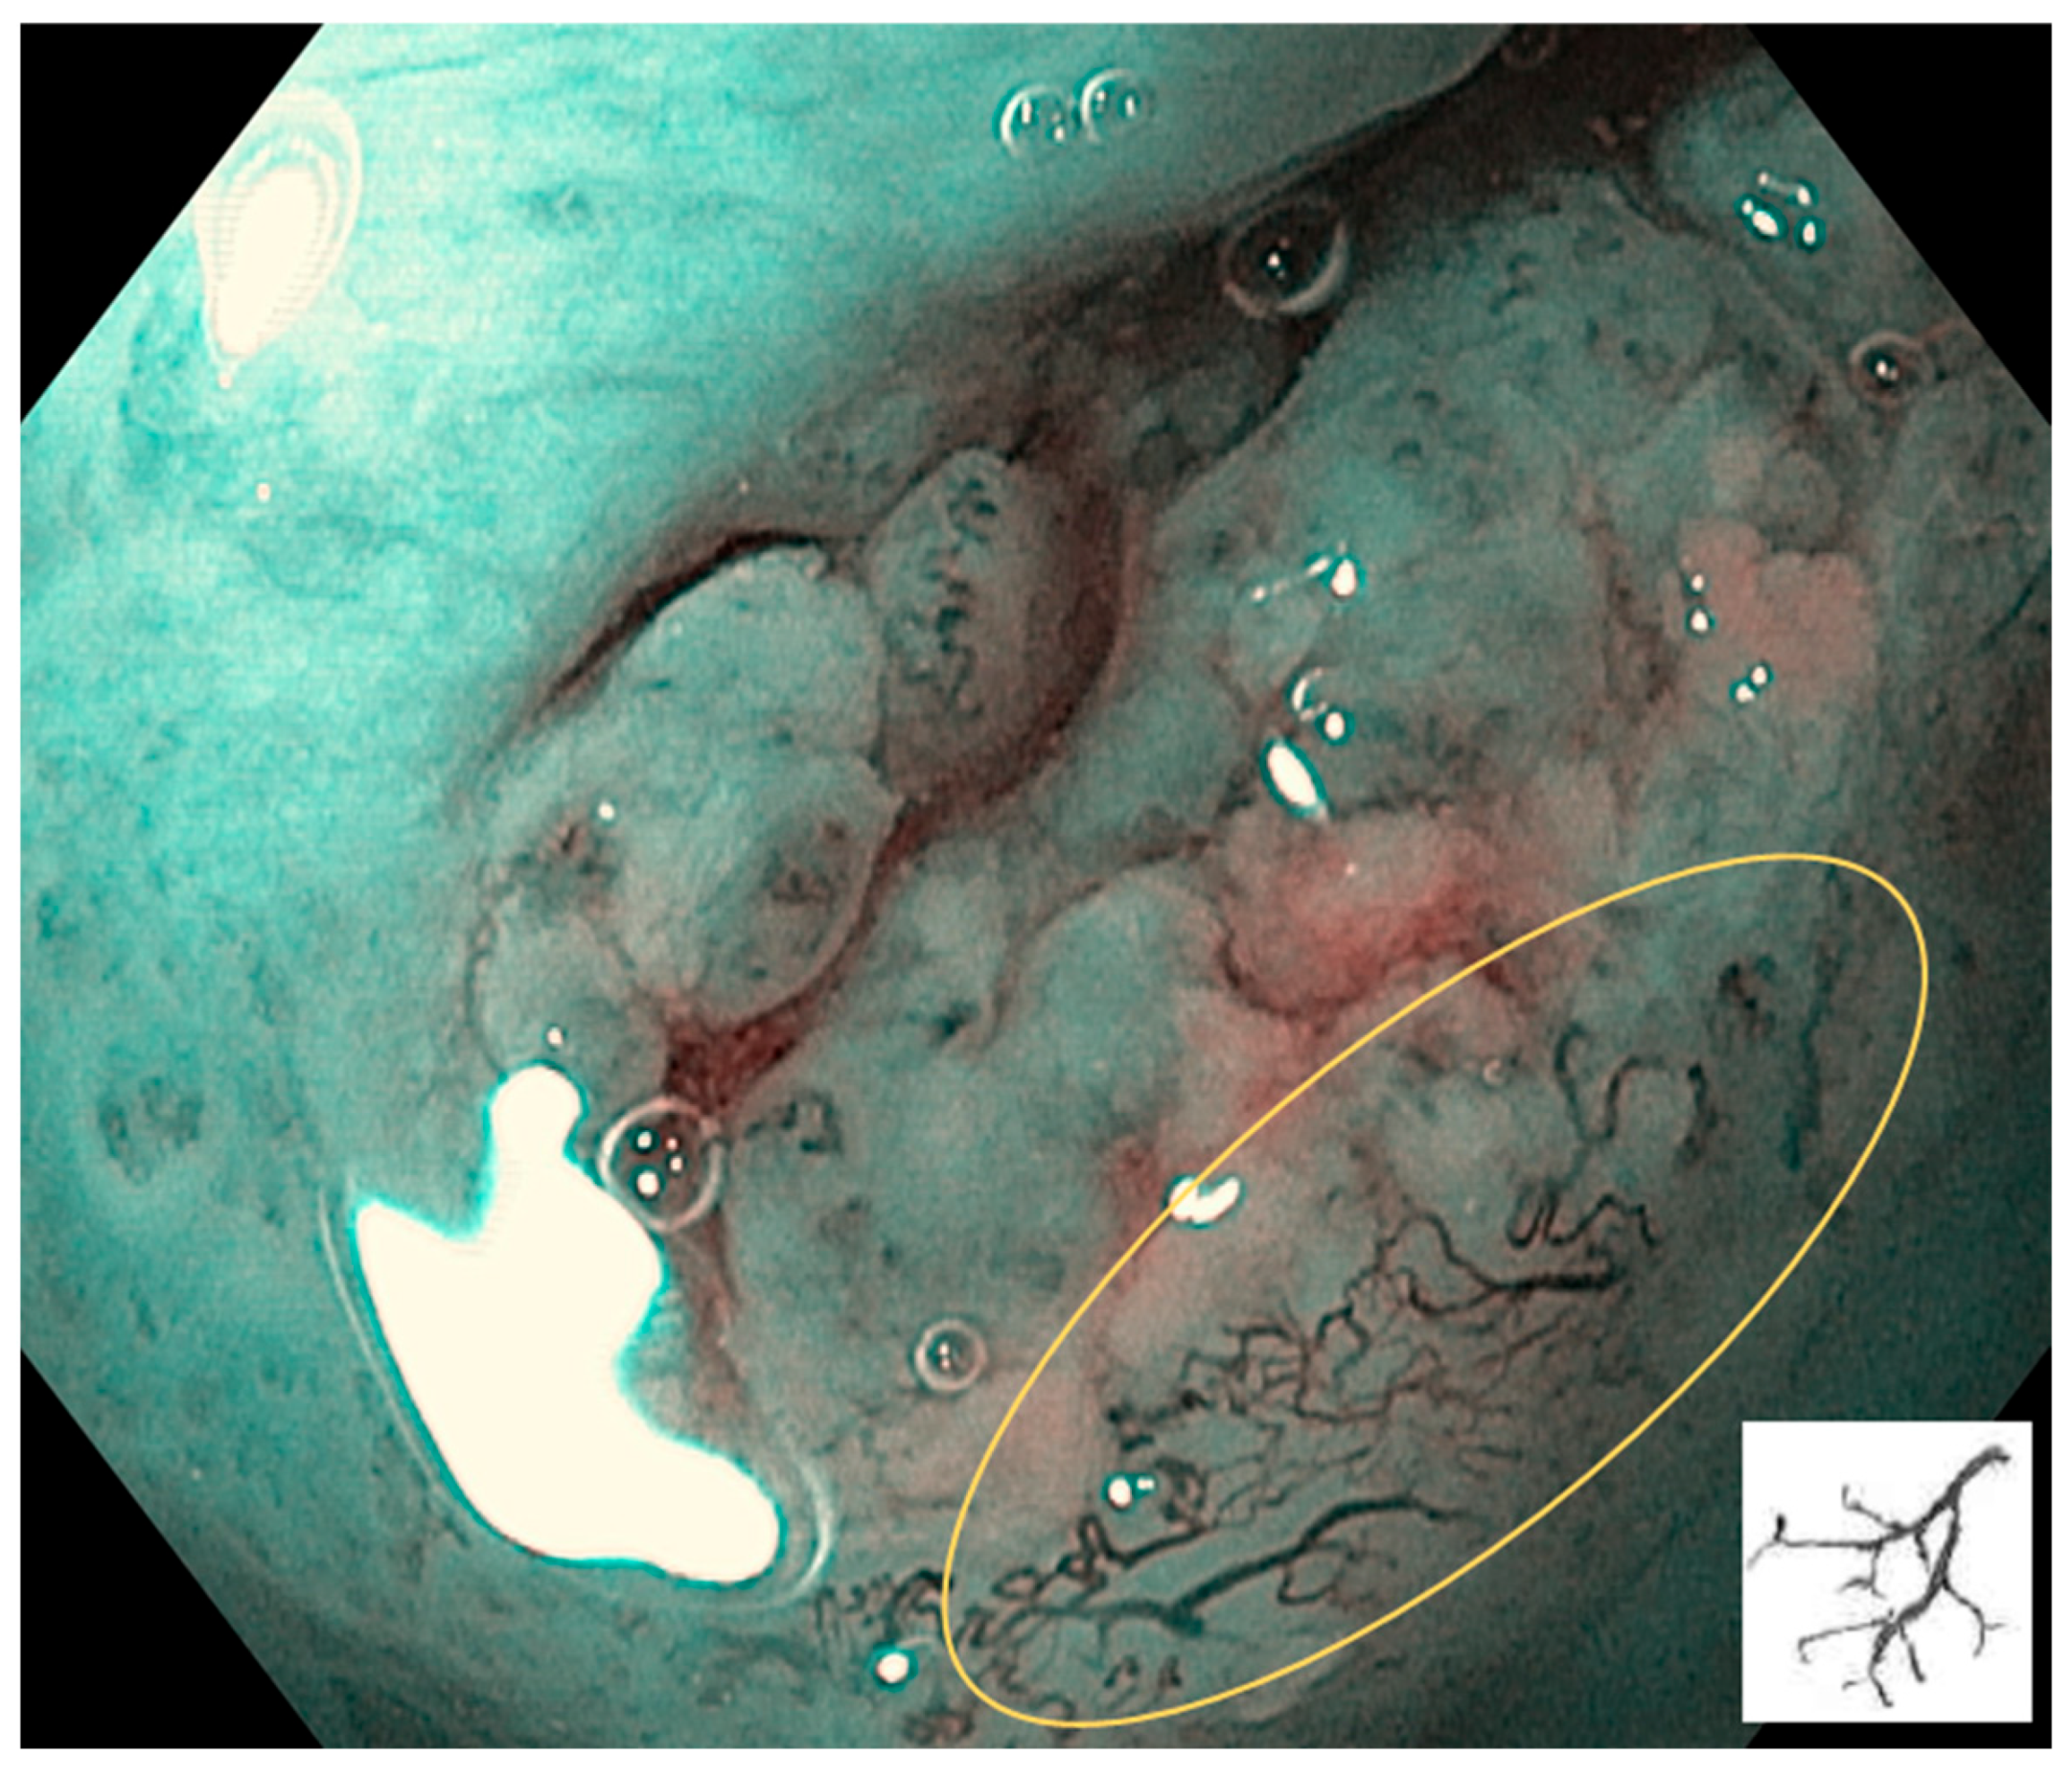

7. Interpretation of IPCLs

8. Limitations of NBI Magnification Endoscopy